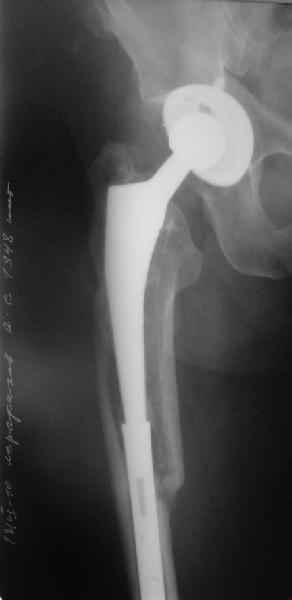

Перелом бедра сросся. Конечность опорная и безболезненная, ходит без трости. Ножка, похоже, реинтегрировалась, как и надеялись. Снимки и фото в приложении. Комментарии приветствуются.

Надо ли что-то делать дальше, как полагаете? Убрать винты? Убрать "удлинитель ножки"? Или оставить все, как есть? Спасибо заранее.